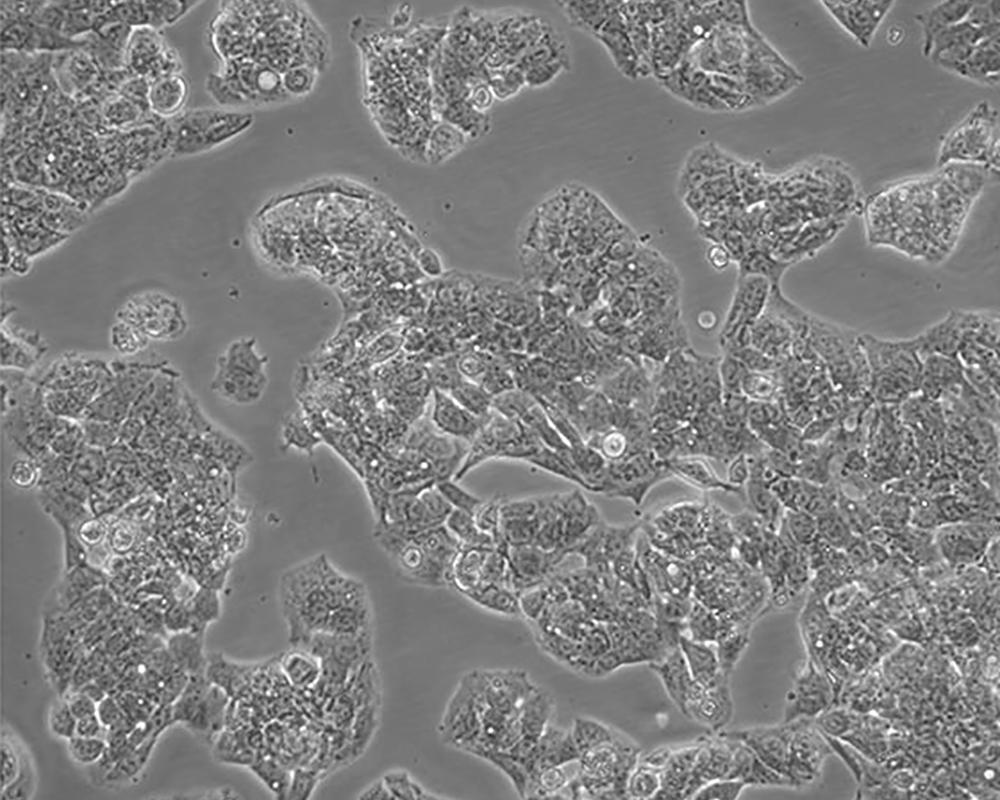

Hep G2

產品名稱 Hep G2

中文名稱 人肝癌細胞

組織來源 liver

細胞種屬 Homo sapiens, human

生長特性 adherent

培養基 MEM+10% FBS+1% P/S

形態特征 epithelial

傳代方法 1:2-1:3

細胞描述 該細胞來源于一名15歲的白人少年的肝癌組織。該細胞表達甲胎蛋白、白蛋白、α-2-巨球蛋白、α-1-抗胰蛋白酶、轉鐵蛋白、α-1-抗凝乳蛋白酶、結合珠蛋白、銅藍蛋白、纖溶酶原、補體C4、C3激活物、纖維蛋白原、α-1酸性糖蛋白、α-2-HS-糖蛋白、β-脂蛋白、視黃醇結合蛋白;表達胰島素受體和胰島素樣生長因子IGFⅡ的受體;該細胞具有3-羥基-3-甲酰輔酶A還原酶和肝甘油三酯脂肪酶的活性。目前尚未證明該細胞中有HBV基因組。